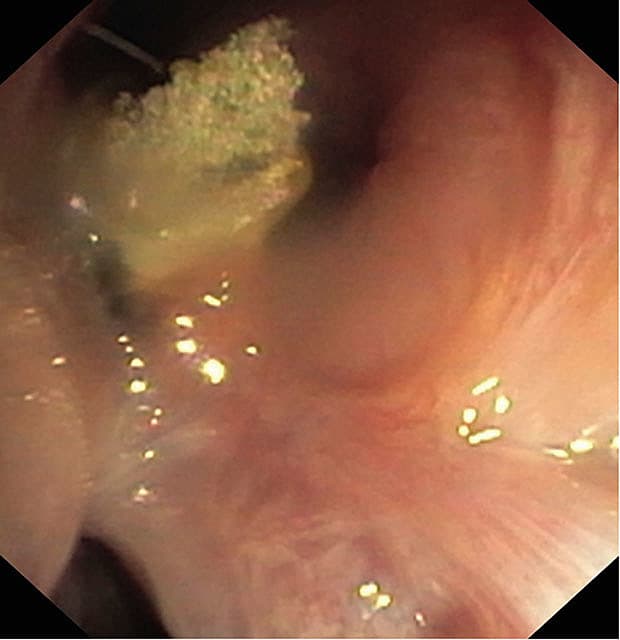

En 71-årig kvinde havde sarkoidose og sequelae i form af recurrensparese og bronkialstenose ved venstre overlap og behov for gentagne bronkiedilatationer, hvorfor hun vedvarende var blevet behandlet med lavdosisprednisolon. I 2011 blev hun desuden behandlet for aspergillose (Aspergillus nidulans og A. candidus). Gennem knap et år blev der observeret en granulationspolyp ved intermediærcarina. På grund af funktionsdyspnø med nedsat gangdistance og træthed blev der foretaget en ny bronkoskopi. Granulationspolyppen

indeholdt svampehyfer og blev fjernet.

I bronkieskyllevæsken var der vækst af Enterobacter cloacae og A. nidulans. En histologisk undersøgelse viste talrige mikroforkalkninger og ødematøst granulocytinfiltreret granulationsvæv beklædt med kvæstet pladeepitel. Der blev iværksat behandling med meropenem og ciprofloxacin i ti dage samt amfotericin B-

inhalation og posaconazol. Klinisk og bronkoskopisk kontrol efter en måned viste ingen tegn til recidiv eller toksicitet. Forløbet viser, at sarkoidose kan kompliceres af skimmelsvampinfektion [1].